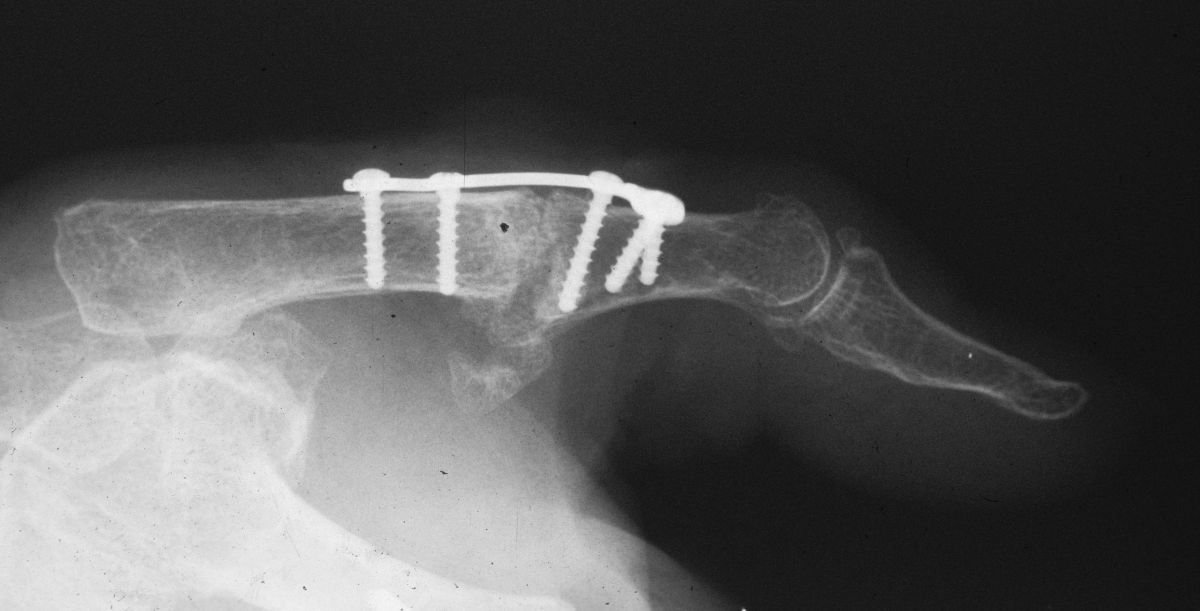

| This patient had chronic

pain and instability from an old radial collateral ligament rupture

followed by both metacarpophalangeal and sesamoid metacarpal arthritis |

| The Synthes mini fragment

system was used, with a lag screw across the fusion site and

sesamoid excision. |

| Although the patient healed

uneventfully, the screws seem excessively large for these bones. |